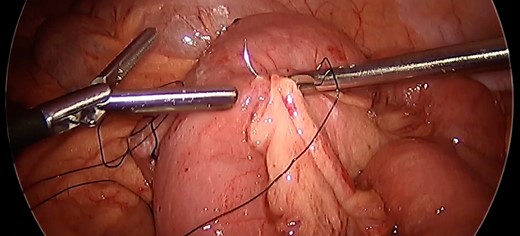

Given the propensity of the distal Roux limb to intussuscept into the enteroenterostomy, enteropexy was performed to eliminate its travel past the anastomosis. The distalmost aspect of the Roux limb was sutured with two pieces of running 3-0 silk to the end of the staple line on the biliopancreatic limb. Two additional sutures were placed slightly more upstream anchoring the roux limb to the mesentery of the transverse colon. An additional 3-0 silk suture was placed on the opposite side of the distal Roux limb anchoring it to the nearby mesenteric root. (Fig. 3) A 3–0 silk suture was placed to fix the common channel to the biliopancreatic limb to similarly limit the risk for intussusception of that limb. After this procedure, the small bowel was immobilized such that there was no longer predisposition for intussusception at the Roux-en-Y enteroenteric anastomosis (Fig. 4).

Anchoring bowel to mesenteric root. Nonabsorbable polyfilament suture placement between bowel and nearby mesenteric root limiting bowel mobility toward the anastomotic junction to prevent intussusception.